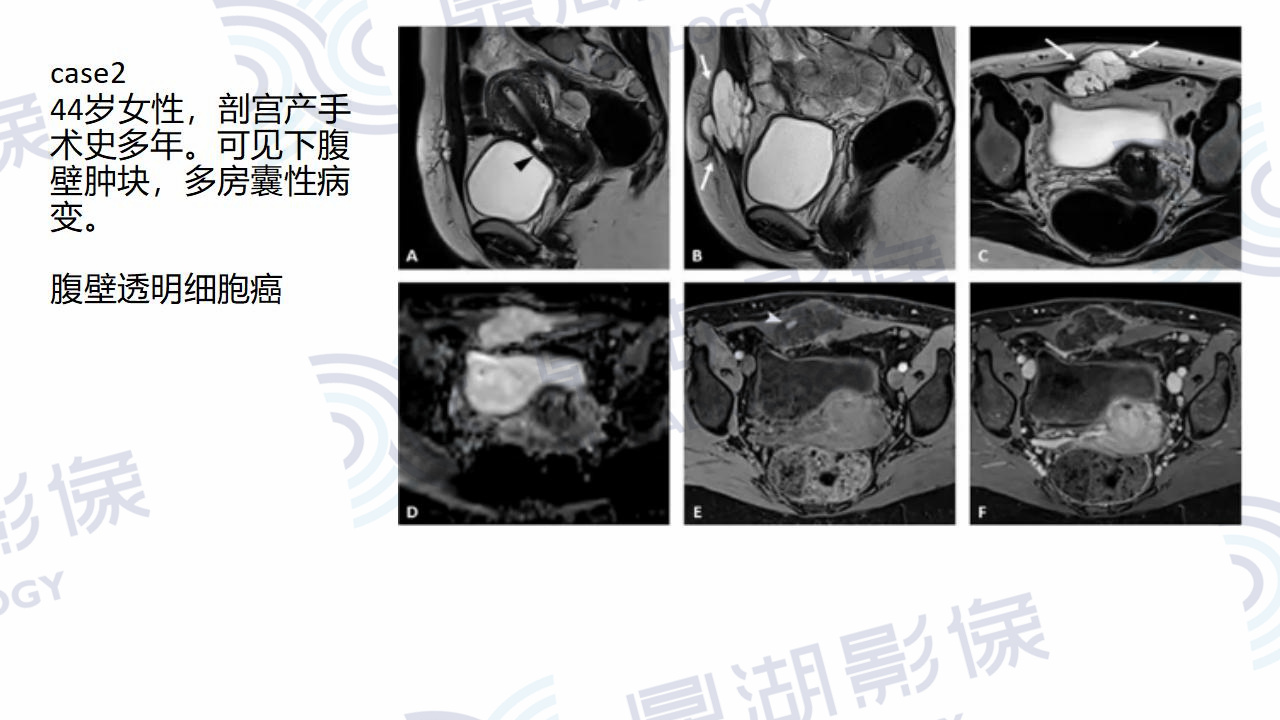

腹壁透明细胞癌

主诉:发现右下腹包块多年,自觉包块增大1年。

患者于一年前出现腹痛,查体提示右下腹包块,未行治疗。一年后复查腹部肿块增大,肿瘤标志物未见异常。剖宫产及腰椎间盘突出手术史。